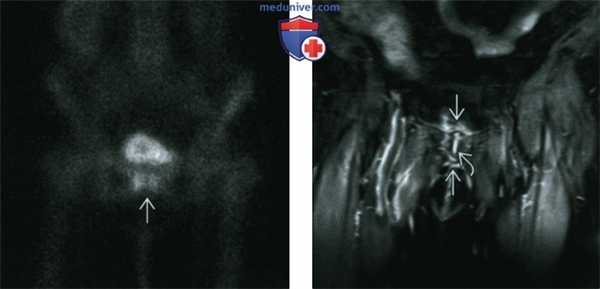

(Слева) МРТ Т2ВИ, режим подавления сигнала от жира, косой аксиальный срез: у футболиста 30 лет с левосторонней болью в паху определяется обширный отек обеих лобковых костей в передне-заднем направлении, с неровностью суставной поверхности, субхондральным склерозом и кистами. Такой ОЛК является по крайней мере подострым, если не хроническим.

(Справа) MPT, STIR, косой коронарный срез: у этого же пациента вновь определяется субхондральный склероз и формирование кисты в дополнение к обширному отеку костного мозга. (Слева) МРТ Т1ВИ, коронарный срез: у футболиста 18 лет, через год после постановки диагноза ОЛК, определяется эрозия и склероз субхондрального слоя кости.

(Справа) МРТ Т2ВИ, режим подавления сигнала от жира, аксиальный срез: у этого же пациента определяется субхондральная эрозия, а также двусторонний и асимметричный отек костного мозга и пролиферативные изменения кости в картине, имитирующей агрессивный артрит. (Слева) МРТ Т2ВИ, режим подавления сигнала от жира, коронарный срез: у спортсмена с преобладанием левосторонней боли в паховой области над правосторонней определяется субхондральный отек костного мозга, также больше слева. Криволинейный сигнал от жидкости в виде пучка латеральнее симфиза указывает на вторичную расщелину, свидетельствующую о травме апоневроза прямой/приводя-щей мышцы. Односторонняя вторичная расщелина служит достоверным признаком на стороне симптомов.

(Справа) Сцинтиграфия костей с МДФ, меченной Тс-99, в передне-задней проекции: у этот же пациента определяется интенсивное поглощение радиометки вокруг ЛС при картине, схожей с субхондральным отеком костного мозга, который визуализируется на МРТ при остром ОЛК. ОЛК часто не визуализируется или слабо выражен при рентгенографии. (Слева) МРТ Т2ВИ, режим подавления сигнала от жира, косой аксиальный срез: у женщины 32 лет с левосторонней болью в паху и правосторонней болью в тазобедренном суставе определяются асимметричный субхондральный отек костного мозга слева и гипертрофия капсулы ЛС с ранними пролиферативными изменениями, свидетельствующие о ОЛК вследствие дестабилизирующей травмы.

(Справа) MPT, STIR, коронарный срез: у этой же пациентки определяется правосторонний сакроилиитв. ОЛК и сакроили ит часто встречаются у пациенток после родов (в этом случае через семь месяцев после рождения ребенка. (Слева) МРТ Т1ВИ, косой аксиальный срез: у игрока в лакросс 19 лет с пубалгией определяется неровность края лобкового симфиза слева с несращенным патологически гипоинтенсивным апофизом бугорка лобковой кости слева и реципрокным отеком коан от мозга справа. ОЛК может проявляться в виде апофизита бугорка лобковой коаи у молодых спортсменов.

(Справа) MPT, STIR, коронарный срез: определяется более хроническая и зрелая картина ОЛК с отеком коаного мозга и пролиферативные изменения кости.